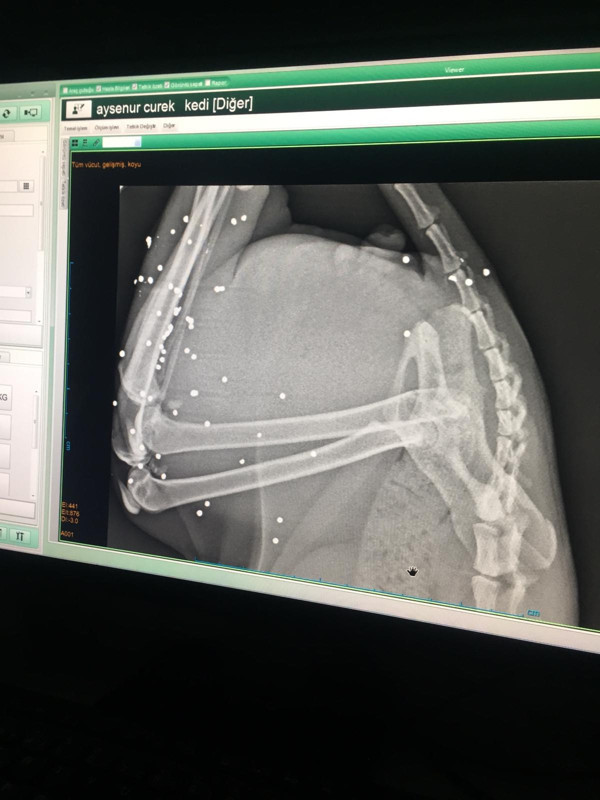

Eve gelerek kediyi alıp kliniğe götüren veteriner tarafından filmleri çekilen kedinin vücudunun arka ayaklarının olduğu bölgede tüfekle ateş edilmesine bağlı çok sayıda saçma izine rastlandı. Güçlükle yürüyen ve arka ayaklarının üzerine güçlükle basan kedinin tedavisine başlanırken, Manavgat İlçe Jandarma Komutanlığı ekipleri tarafından olayla ilgili inceleme başlatıldı.

Veteriner Hekim Atila Sargın, Şenay Yılmaz’ın kendisini aramasından sonra olaydan haberdar olduğunu belirterek, "Gelip baktığımda kedinin durumunun kötü olduğunu gördüm. Hemen aldım kliniğe götürdüm. Röntgeni çekince gördüm ki kedinin arka tarafında çok sayıda saçma var. Yani kedinin arka tarafında tüfekle ateş edilmiş” dedi.